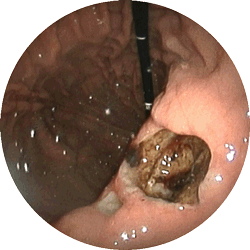

胃潰瘍3

胃潰瘍

心窩部の痛みが続き来院